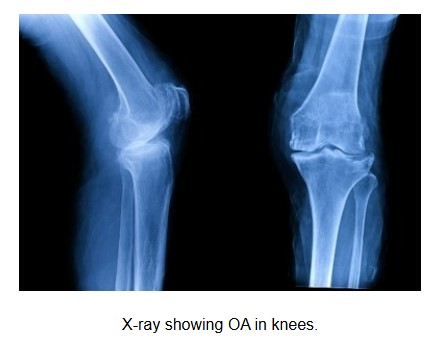

OA is often diagnosed through taking history and physical examination. X-rays of the affected joints may be taken to support or confirm the diagnosis. When the diagnosis is less certain or complications (e.g. nerve impingement) are suspected, additional tests like MRI (e.g. spine) may be performed.